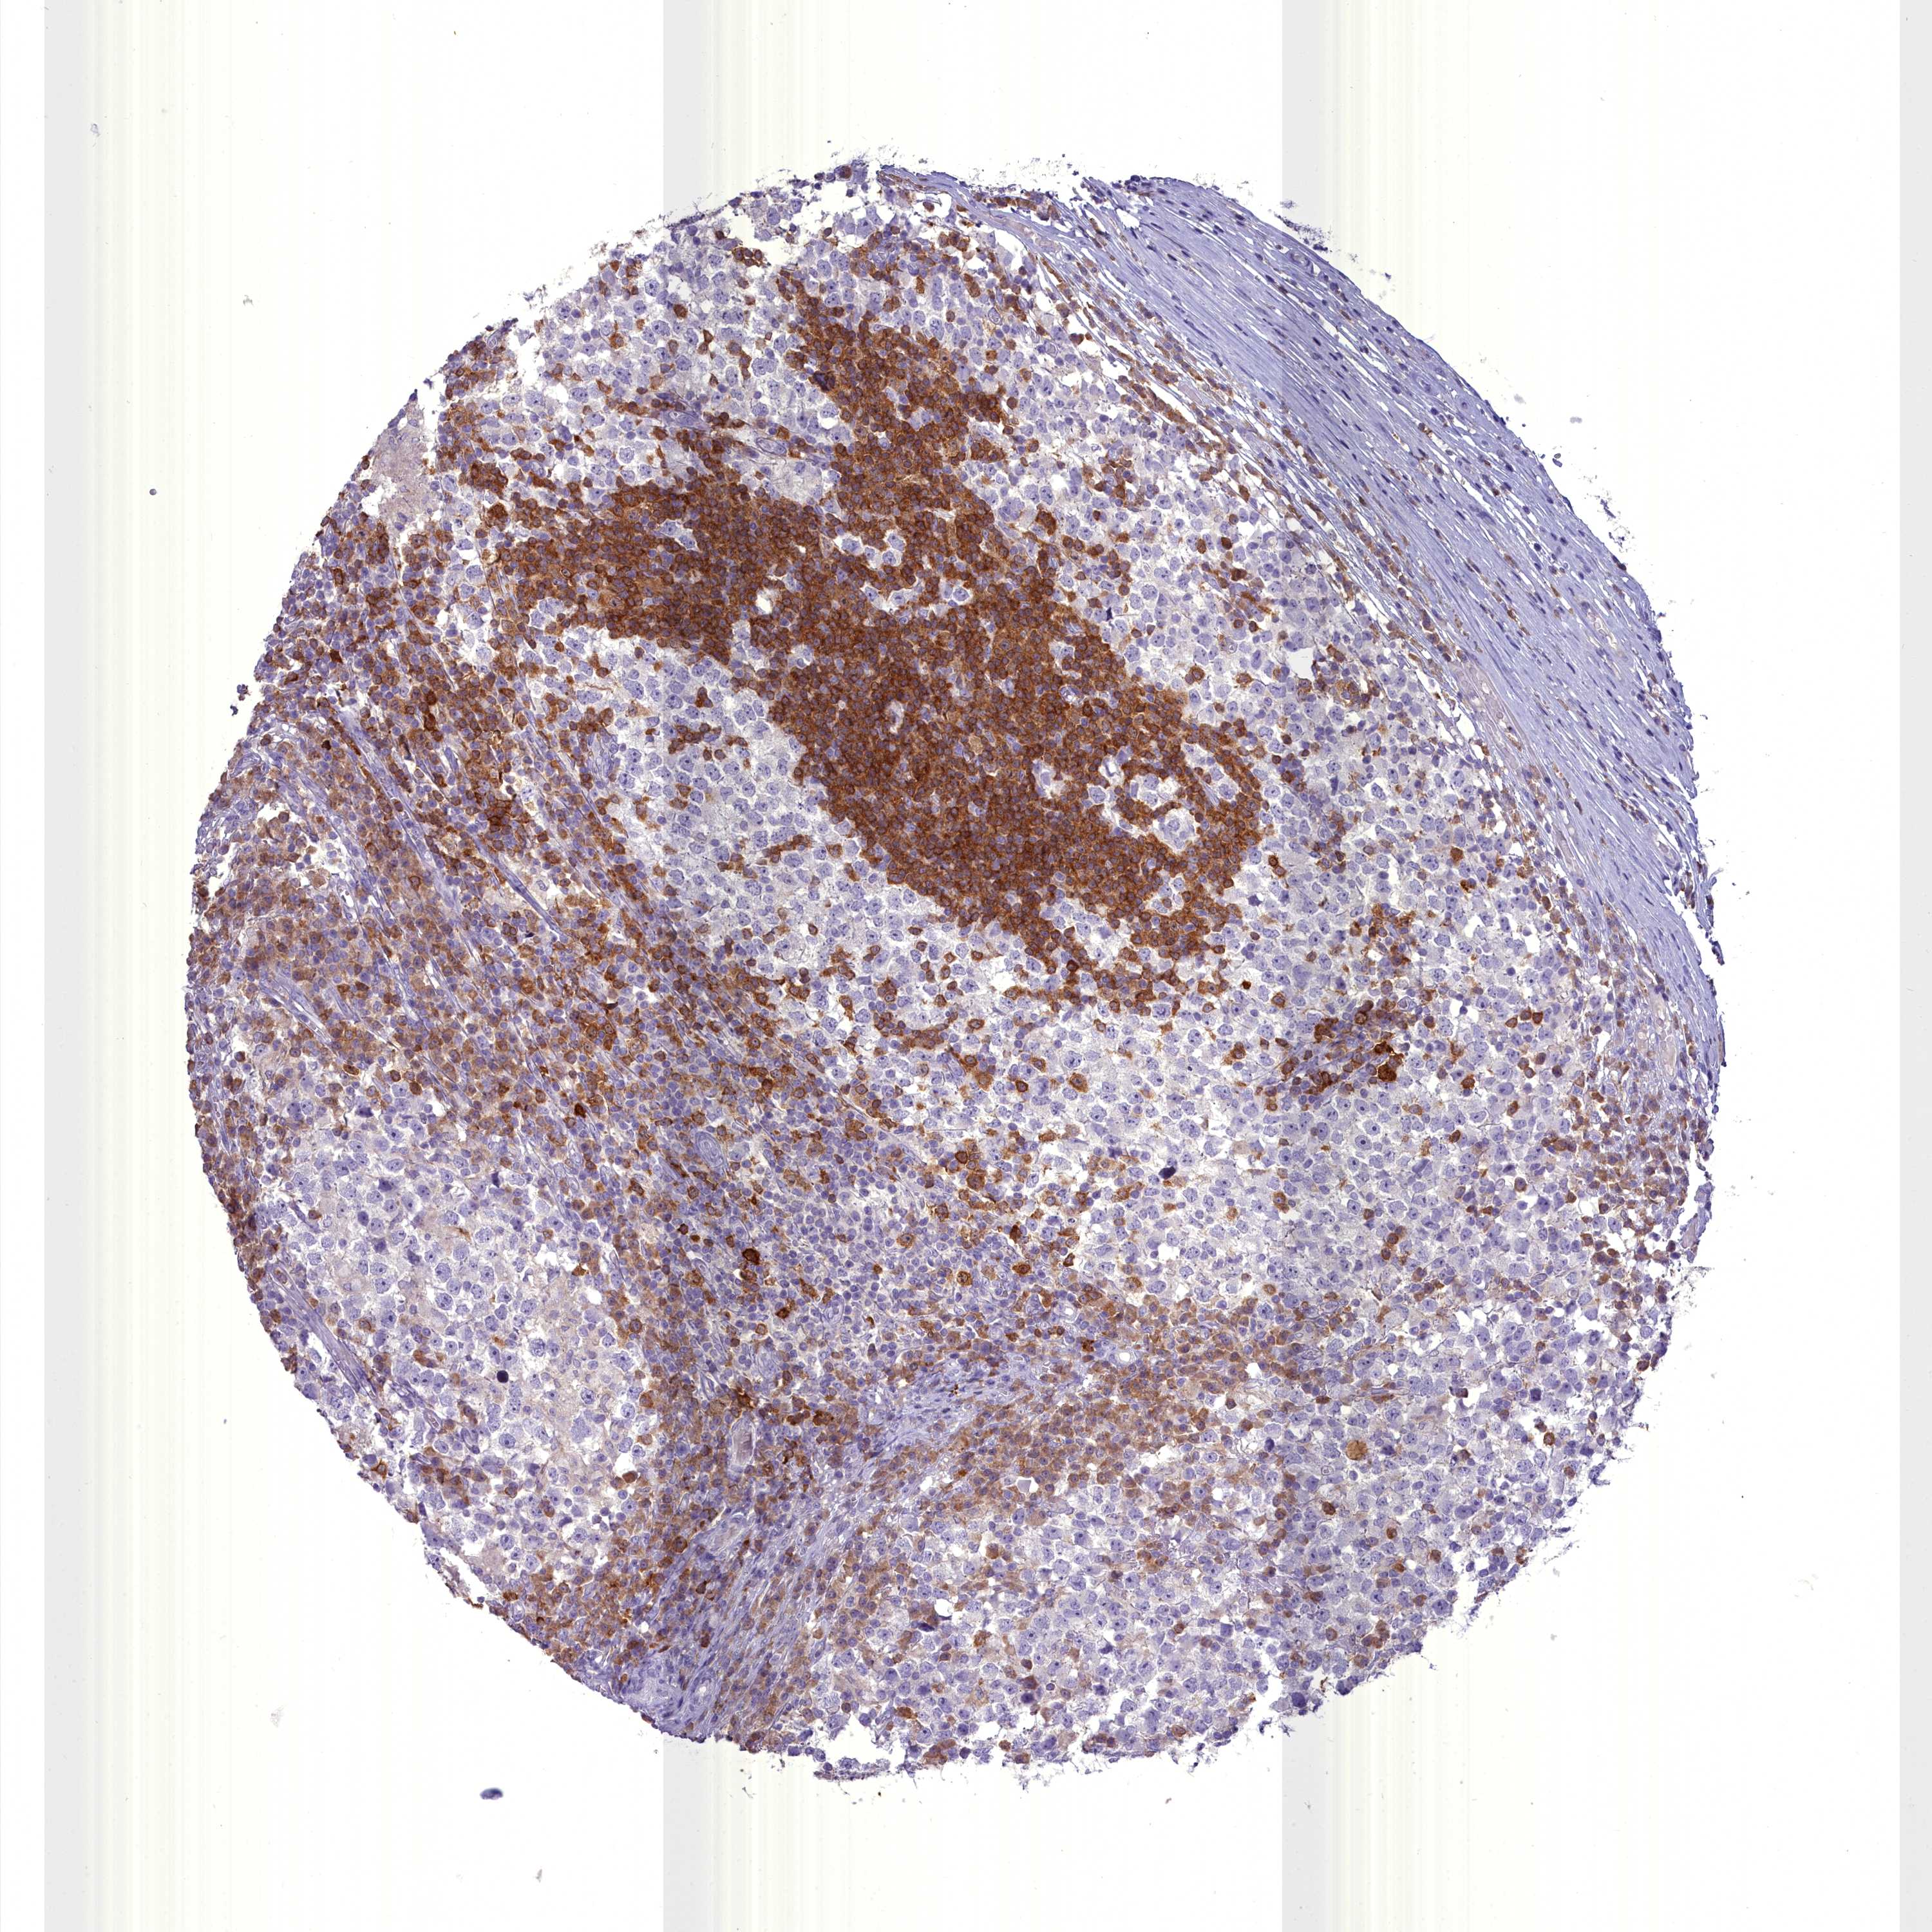

TESTIS CANCER - Protein expressioni

A mouse-over function shows sample information and annotation data. Click on an image to view it in a full screen mode. Samples can be filtered based on level of antibody staining by selecting one or several of the following categories: high, medium, low and not detected. The assay and annotation is described here.

Note that samples used for immunohistochemistry by the Human Protein Atlas do not correspond to samples in the TCGA dataset.

Antibody stainingi

Antibody staining in the annotated cell types in the current human tissue is reported as not detected, low, medium, or high, based on conventional immunohistochemistry profiling in selected tissues. This score is based on the combination of the staining intensity and fraction of stained cells.

Each image is clickable and will lead to virtual microscopy that enables deeper exploration of all samples and also displays staining intensity scores, fraction scores and subcellular localization as well as patient and tissue information for each sample.

Antibody CAB009333

Antibody CAB016291

Carcinoma, Embryonal, NOS

Seminoma, NOS